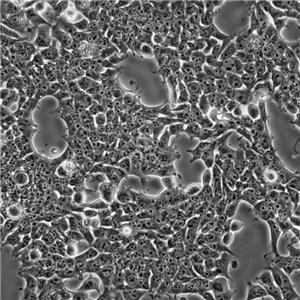

EL4细胞系的生长特性是悬浮生长,即细胞在培养液中自由漂浮。这种细胞系的形态学表现为淋巴瘤细胞样,具有圆形或椭圆形细胞核和胞质。EL4细胞系的应用主要集中在科研领域,研究人员可以利用这种细胞系来研究肿瘤的发生发展、免疫应答机制以及抗肿瘤药物的筛选和评价等。

形态特征:EL4细胞呈圆形或椭圆形,具有多个核和核分裂像。

通过观察鼠T细胞淋巴瘤细胞株EL4细胞能否被小鼠巨细胞病毒(Murine cytomegalovirus,MCMV)感染,及其感染前后EL4小鼠淋巴瘤细胞系形态的变化,及MCMV感染对EL4细胞凋亡的影响,为寻求有效的T细胞淋巴瘤治疗方法提供新的方向。

结果:MCMV感染后,EL4小鼠淋巴瘤细胞系体积增大,细胞核不规则,见折基金项目:国家自然科学基金,81470344叠扭曲。与正常对照组相比,各感染组EL4小鼠淋巴瘤细胞系存活率降低,凋亡率增加(P<0.05),凋亡蛋白P53、Bax/Bcl-2、Cleaved-caspase3、Caspase8表达均上调,以MOI=10感染组在感染后第5天最为明显。与MCMV感染组(MOI=60)比较,MCMV+GGV组EL4细胞内MCMV DNA含量降低(P<0.05),EL4细胞凋亡率及凋亡蛋白P53、Caspase8、Bax/bcl-2表达降低(P<0.05)。